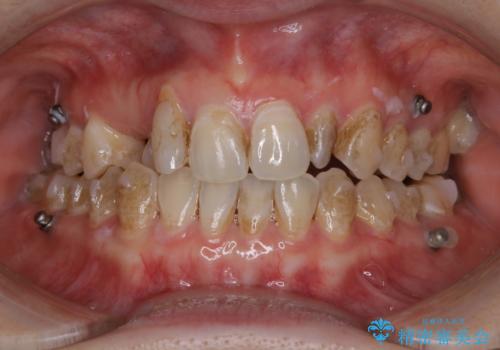

ワイヤー矯正終了時に装置除去と合わせてPMTC

担当医 歯科衛生士